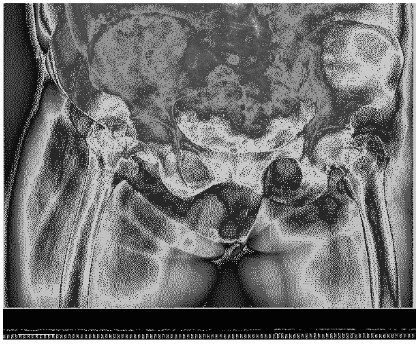

Total hip replacement was performed for her and she was allowed to walked weight-bearing with the help of a walker, 1 week later she was discharged from the hospital (Figure 4).

Figure 4: Case 1 hip replacement

FNS internal fixation was done for the fracture successfully. And she was permitted to sit in wheel-chair or stand on the unaffected leg within short period post-operatively (Figure 8).

Figure 8: Case 2 FNS internal fixation of femoral neck.

The interval between femoral neck fractures after TKR was 2 to 17 months, with an average of 8 months (4 and 12 months in our two cases, respectively). Amite Pankaj [11] proposed that early X-ray examination sometimes fails to detect femoral neck fracture, and safer MRI can provide earlier diagnosis. The early diagnosis is important, because it helps to the conservative treatment and avoid the shifting after the fracture, thus avoiding surgical treatment [2,8,10]. In our case, both patients experienced pain in the groin and presented to the doctor 1 month later. The patients did not pay much attention to these symptoms. Therefore, this complication should be highly suspected when ipsilateral hip pain occurs after TKR, especially in patients with poor mobility or obvious osteoporosis.